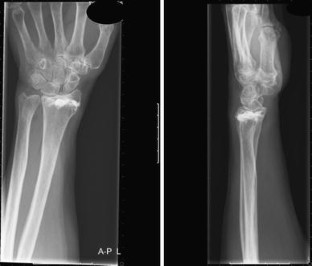

Fig. 2

Distal radius fractures are one of the most common fractures in the elderly females. In this article, we report a case of a distal radius fracture type AO-A3 with dorsal instability, in an older woman with manifest osteoporosis, treated with minimally invasive Cortoss® composite and FFS-wires®. A 63-year-old woman sustained an unstable distal radial fracture of her left wrist after falling from a kitchen step. She underwent an open reduction of the fracture and fixation with two crossed-fixation pins and Cortoss® composite. Post-operative plaster cast immobilization was given for 2 weeks, after which the plaster cast and the fixation pins were removed. At 4 weeks follow-up, she had a good functional result of her left wrist, after 11 months there was a complete return of grip strength with also, except for the palmar flexion, a full return of function. We report here the first case of a successful surgical treatment with Cortoss® composite of an AO-A3 type distal radius fracture.